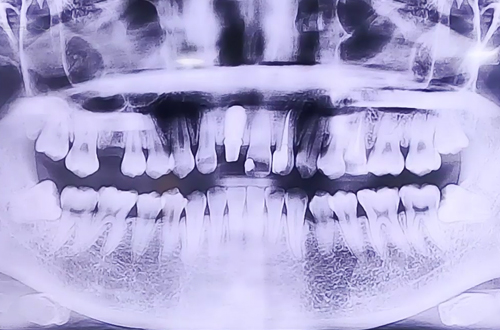

부러진 앞니 임플란트

AFTER

처음엔 자연 치아를 최대한 살리는 방향의 치료를 고려했지만 치아 상태가 그러기 어려워 부러진 앞니를 발치하고 임플란트를 통해 복원하는 방향으로 치료를 진행중이십니다.

현재 식립한 임플란트가 제대로 자리 잡을때까지 임시 치아를 제작해 씌워드린 상태이며, 추후 임플란트가 단단히 자리 잡고 보철이 완성되면 다음 진료일지로 찾아뵙도록 하겠습니다. ^^